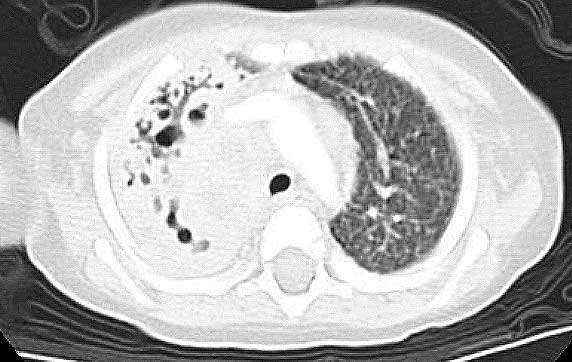

Below are CHEST CT results.

Enlarge

this CHEST CT.

Enlarge this CHEST CT.

WHAT

IS YOUR INTERPRETATION FOR THE CHEST CT?